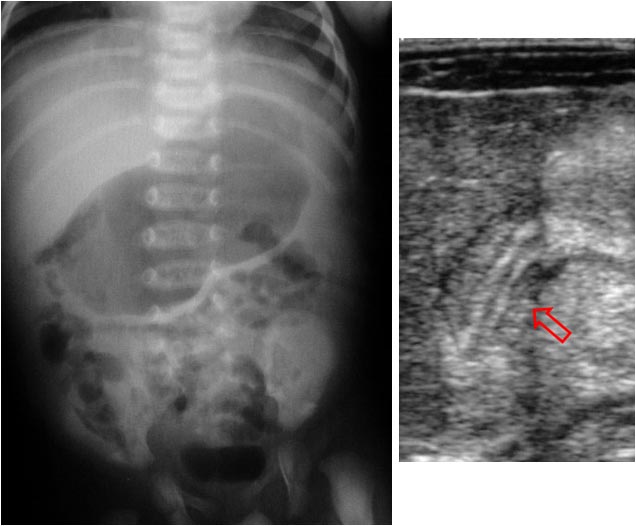

SIGNO DEL HÍGADO AUSENTE

La identificación de aire intestinal en el hemitórax derecho (en la placa de tórax de un neonato) –flecha- permite realizar el diagnóstico de hernia diafragmática congénita. En aquellos casos en los que únicamente se produce la herniación del hígado, el diagnóstico suele ser erróneo. La combinación de la opacificación del hemitórax junto a la presencia de aire intestinal en el cuadrante superior derecho (Signo del hígado ausente), debe sugerir el diagnóstico de hernia hepática intratorácica.